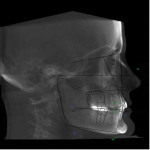

Recognizing the challenges inherent in treating this patient restoratively without correcting the occlusal plane, the patient was referred to the orthodontist. Additional records were taken, including a CBCT scan and an intraoral scan (iTero® Element, Align Technology). The orthodontic findings revealed that the patient was brachyfacial and possessed class I occlusion with mild crowding (Figure 7 and Figure 8).19 Additional findings included that her facial thirds demonstrated correct proportions with a flat to convex profile, she had wear on teeth Nos. 8 and 9 with short clinical crowns and a discrepancy between the vertical position of the anterior and posterior teeth, and she exhibited mild, generalized gingival recession.